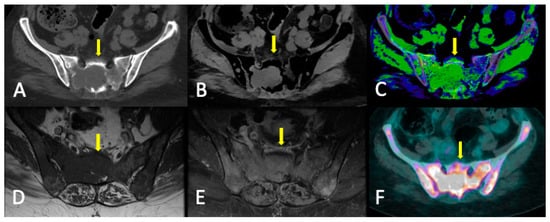

4. WBMRI

4.2. Disease Patterns

- Diffuse pattern: Diffuse disease can be suspected from a diffuse decreased signal on T1WI (either iso- or hypointense to intervertebral discs and muscle) and a diffuse increased signal throughout the marrow on T2FSWI, STIR, or high b-value DWI. Marrow ADC values above 600–700 μm2/s in a nontreated and newly diagnosed patient with MM could be used to increase confidence for the diagnosis of diffuse marrow involvement [33] (Figure 7). Due to potential false-positive findings, diffuse disease in imaging must be supported by bone marrow trephine biopsy [26].

5.1.5. FDG-PET/CT vs. WBMRI